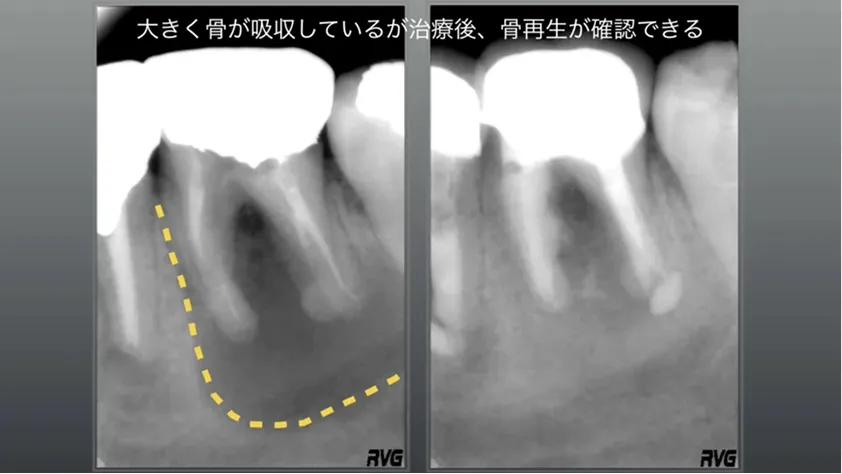

長くて太いメタルポスト(レントゲン上では白い部分)が確認でき、別な歯科医院では長いメタルポストは取れないと言われて来院、術前黄色の点線部分は大きく骨が吸収して、口腔内では時々腫れを繰り返す症状があるとのこと。

通常の根管治療を2回行い、数ヶ月後には骨再生がレントゲン上で現れ、外科をやらなくても通常の根管治療で虎ノ門吉松歯科医院では治す事が可能です。

長いメタルポストで必ず除去して

根管治療を行うことができます

大きく骨吸収しているが、治療後骨再生が確認できます